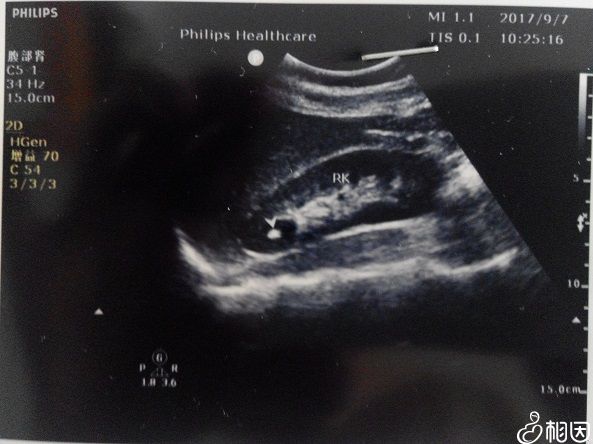

相比于过去的B超检查,四维彩超的优势很明显,其清晰的图像功能使得检查的准确率更高,对于高龄女性来说,四维的排畸功能可以让孕妇尽早确定胎儿情况,并作及时处理,这也是医生建立女性做该项检查的主要原因。

除此之外四维彩超还被称为“0岁宝宝的写真”,医生可以将宝宝的相貌和动作制成VCD,准爸妈可以随时观察录像,有非常大的纪念意义。